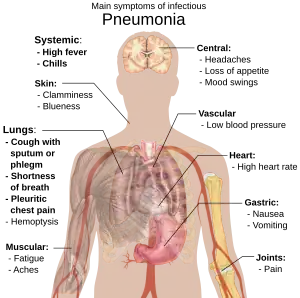

People with infectious pneumonia often have a productive cough, fever accompanied by shaking chills, shortness of breath, sharp or stabbing chest pain during deep breaths, and an increased rate of breathing.[9] In elderly people, confusion may be the most prominent sign.[9]

The typical signs and symptoms in children under five are fever, cough, and fast or difficult breathing.[20] Fever is not very specific, as it occurs in many other common illnesses and may be absent in those with severe disease, malnutrition or in the elderly. In addition, a cough is frequently absent in children less than 2 months old.[20] More severe signs and symptoms in children may include blue-tinged skin, unwillingness to drink, convulsions, ongoing vomiting, extremes of temperature, or a decreased level of consciousness.[20][21]

Bacterial and viral cases of pneumonia usually result in similar symptoms.[22] Some causes are associated with classic, but non-specific, clinical characteristics. Pneumonia caused by Legionella may occur with abdominal pain, diarrhea, or confusion.[23] Pneumonia caused by Streptococcus pneumoniae is associated with rusty colored sputum.[24] Pneumonia caused by Klebsiella may have bloody sputum often described as "currant jelly".[19] Bloody sputum (known as hemoptysis) may also occur with tuberculosis, Gram-negative pneumonia, lung abscesses and more commonly acute bronchitis.[21] Pneumonia caused by Mycoplasma pneumoniae may occur in association with swelling of the lymph nodes in the neck, joint pain, or a middle ear infection.[21] Viral pneumonia presents more commonly with wheezing than bacterial pneumonia.[22] Pneumonia was historically divided into "typical" and "atypical" based on the belief that the presentation predicted the underlying cause.[25] However, evidence has not supported this distinction, therefore it is no longer emphasized.[25]